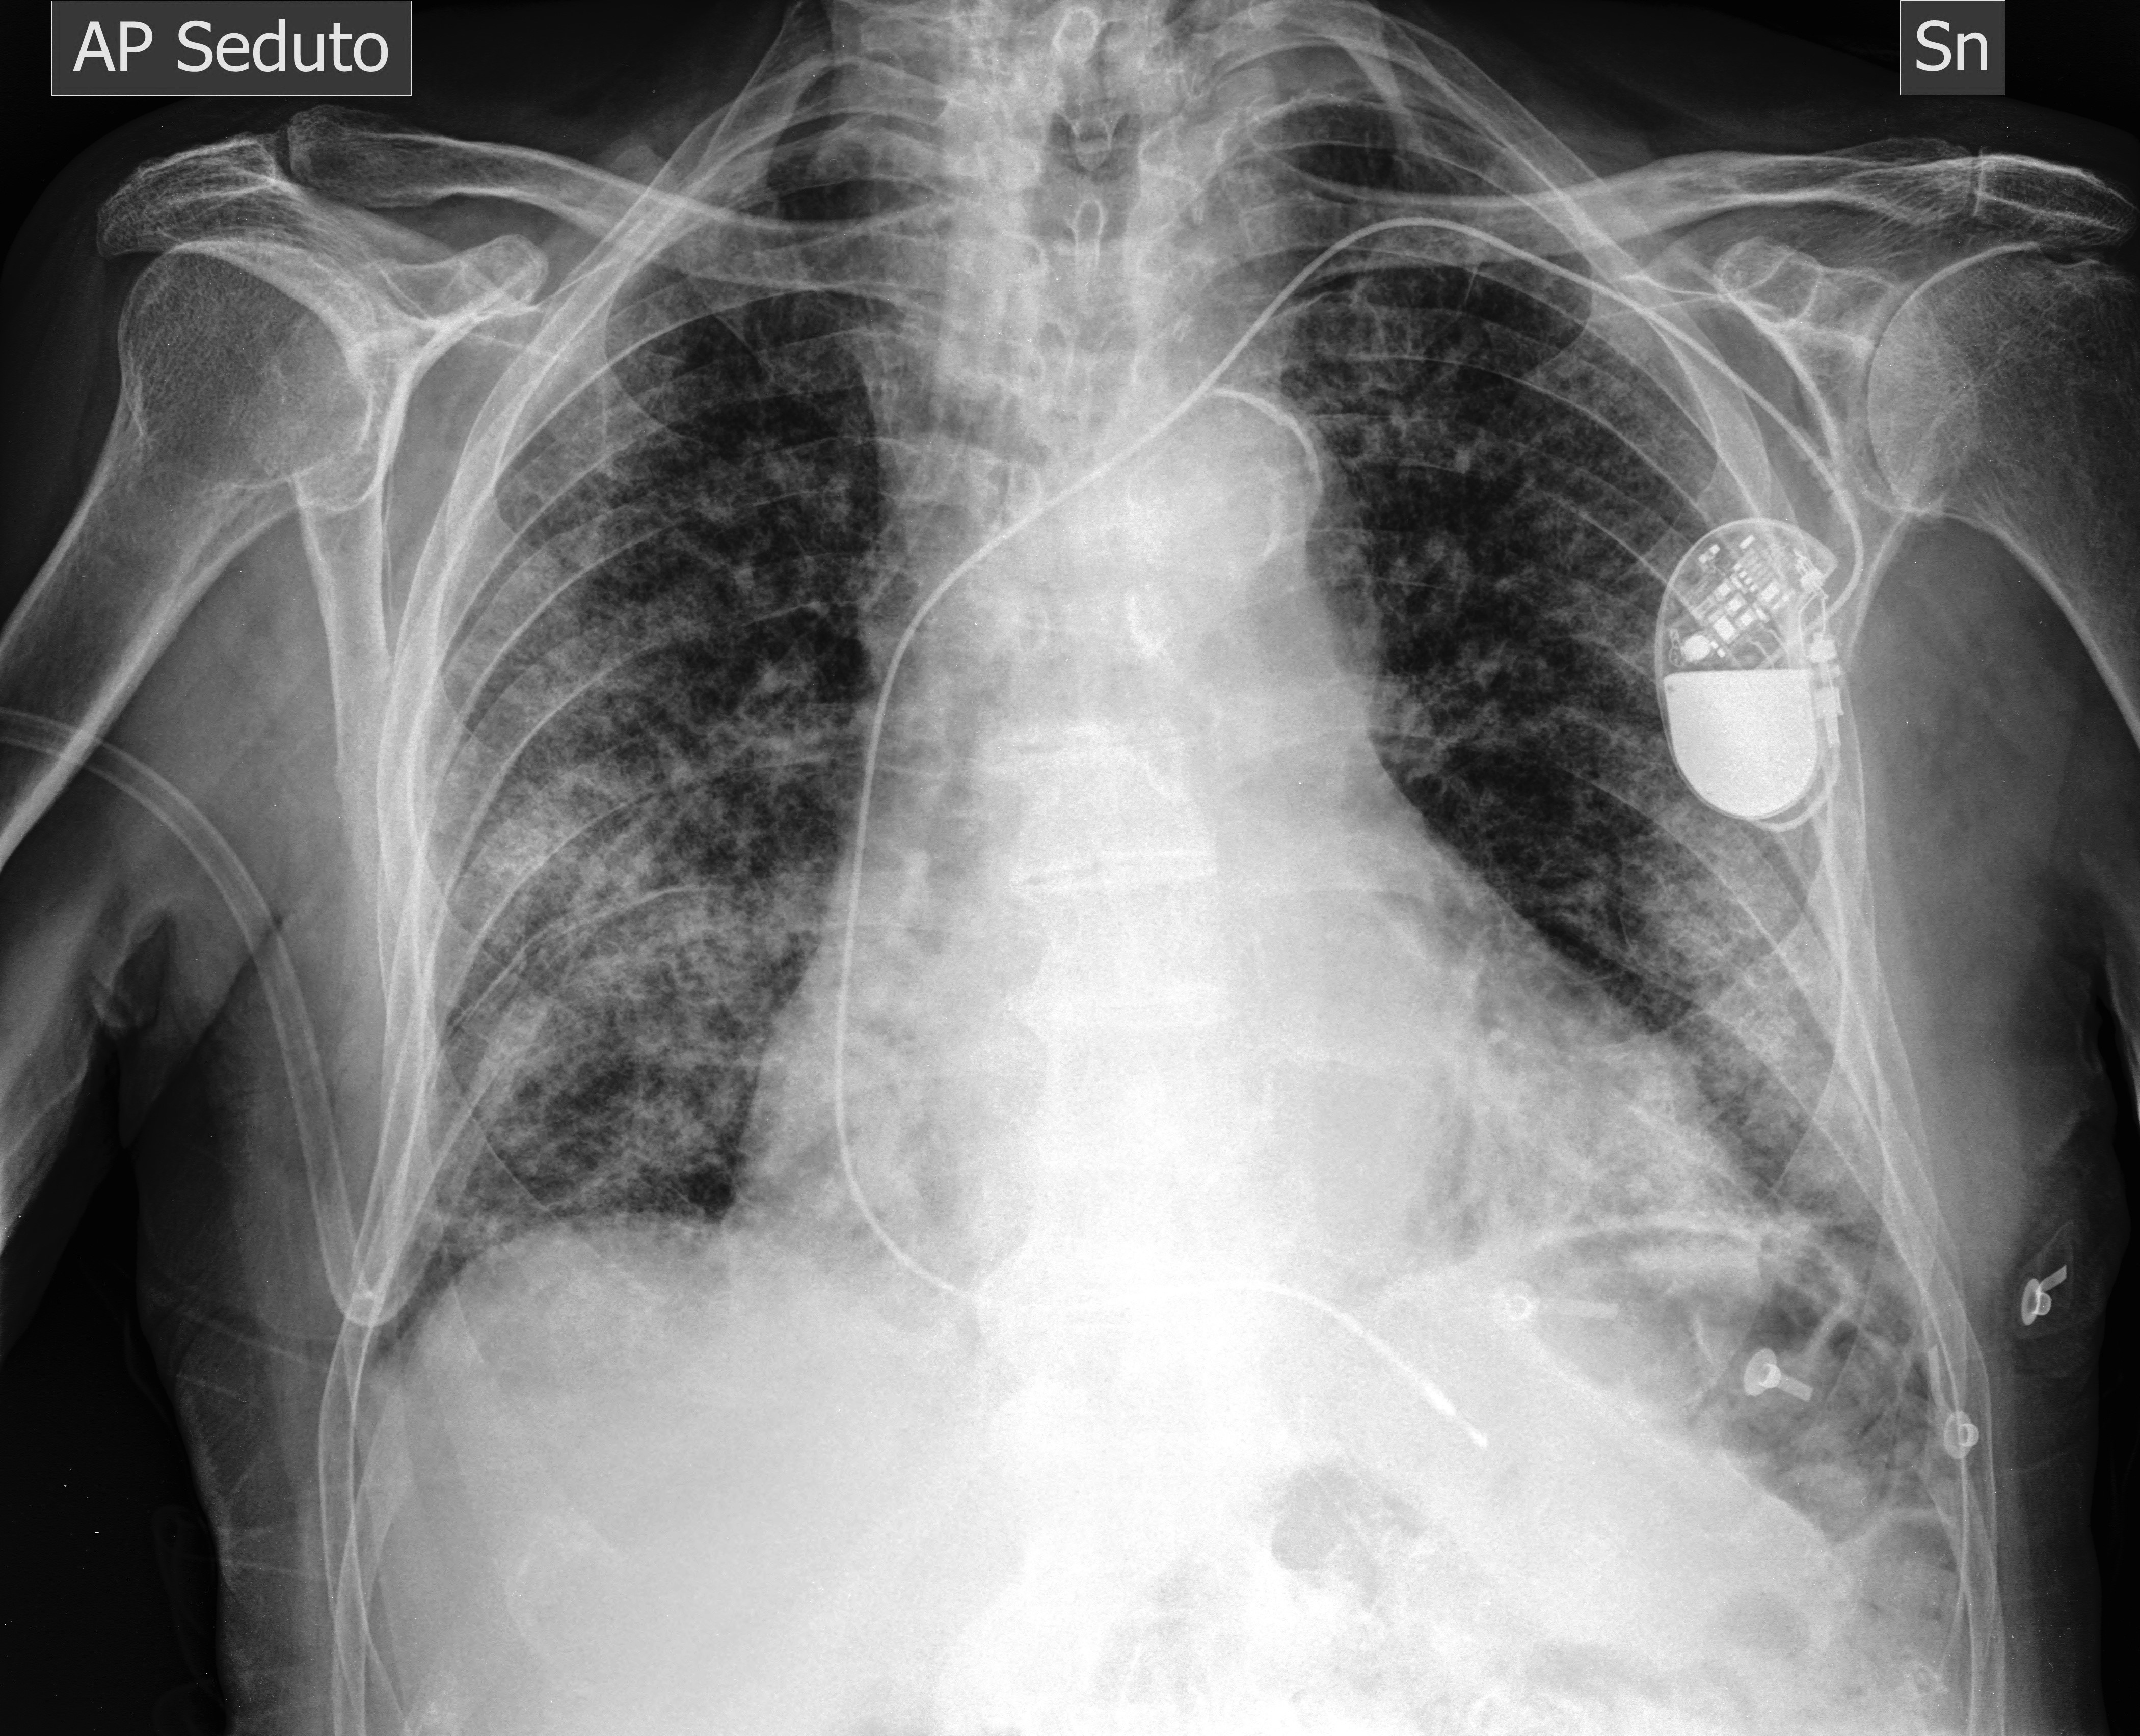

Comparative analysis of X-ray image classification of pneumonia based on deep learning algorithm

In this paper, we compare and analyse the effectiveness of deep learning models such as AlexNet, Vgg, GoogleNet and MobileNet in the task of pneumonia image classification. During the training process, GoogleNet showed the fastest convergence speed, reaching convergence at the 3rd epoch; subsequently, the other three models gradually stabilised. In the end, the loss of AlexNet is 0.426, the loss of Vgg is 0.566, the loss of GoogleNet is 0.936, and the loss of MobileNet is 0.626. By selecting the weights of the round with the best training effect of each model, the results of classification accuracy are obtained: 88.9% for AlexNet, 92.6% for Vgg, and 92.6% for GoogleNet. 92.6%, GoogleNet is 85.2%, and MobileNet is 96.3%. MobileNet demonstrated the best prediction performance on the test set. These results provide a useful reference for the application of deep learning models in medical imaging..